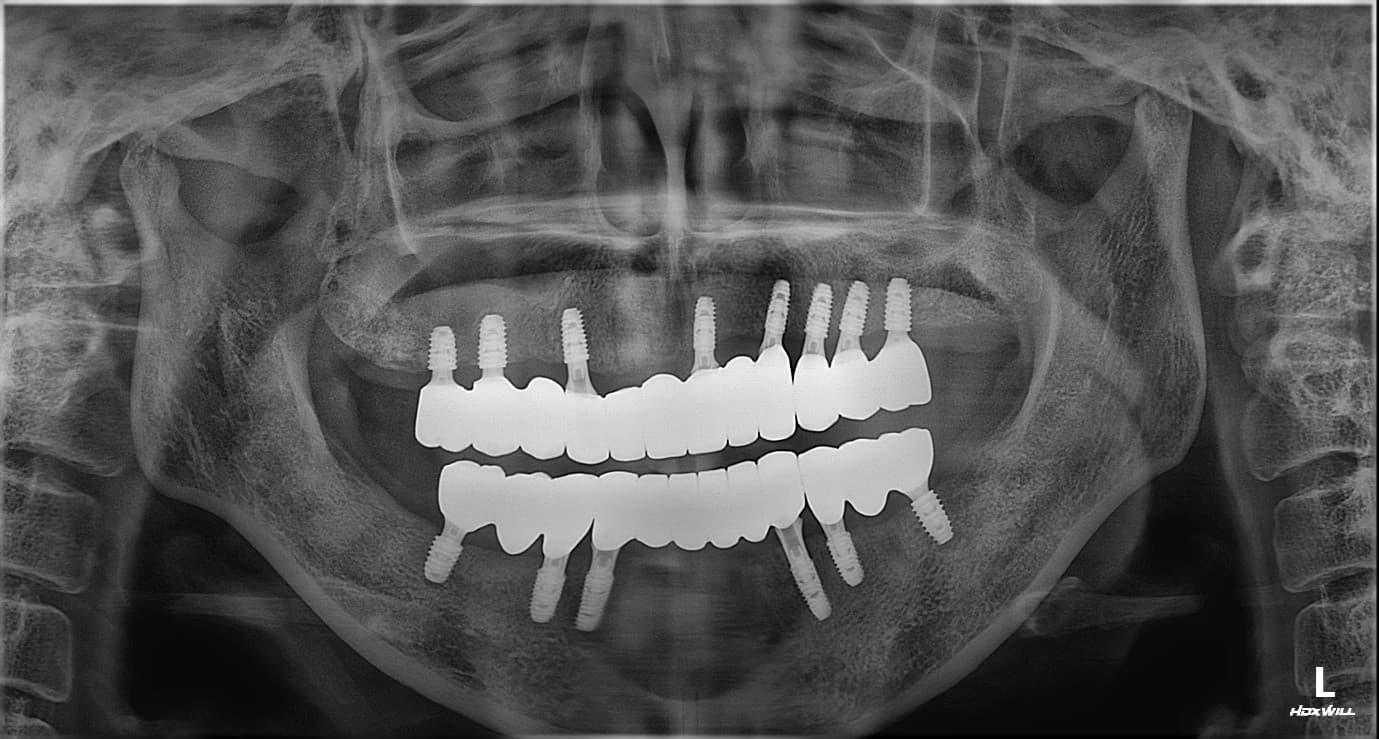

김○님님 치료 사례

치료 후

X-ray